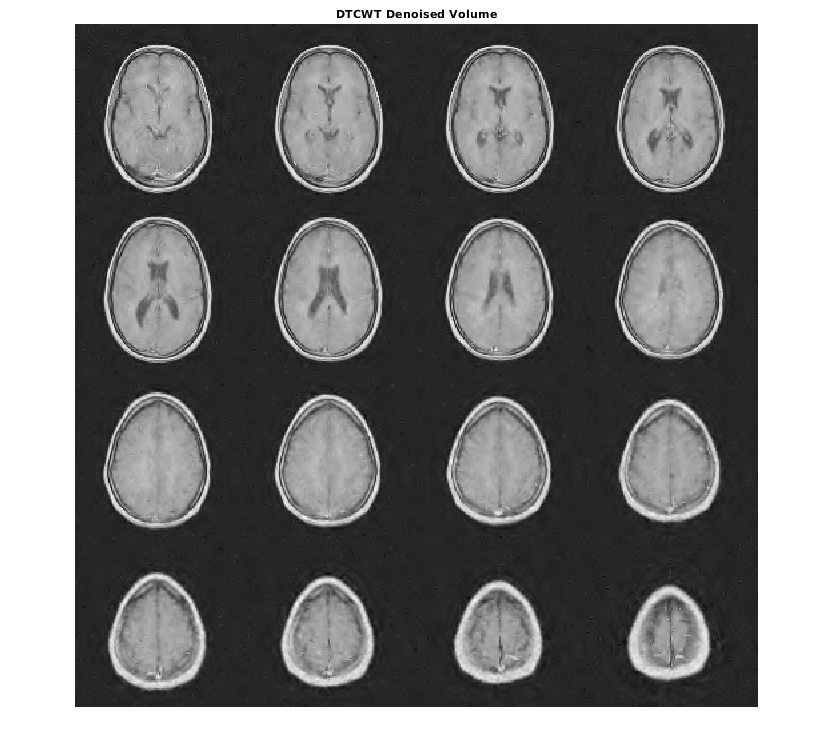

Denoise набор данных MRI вниз к уровню 4 с помощью и DTCWT и DWT. Подобные длины фильтра вейвлета используются в обоих случаях. Постройте получившийся ОСШ как функцию порога. Отобразите denoised результаты и для DTCWT и для DWT, полученного в лучшем ОСШ.

[imrecDTCWT,imrecDWT] = helperCompare3DDenoising(origMRI,noisyMRI);

figure montage(reshape(imrecDTCWT,[128 128 1 16]),'DisplayRange',[]) title('DTCWT Denoised Volume')